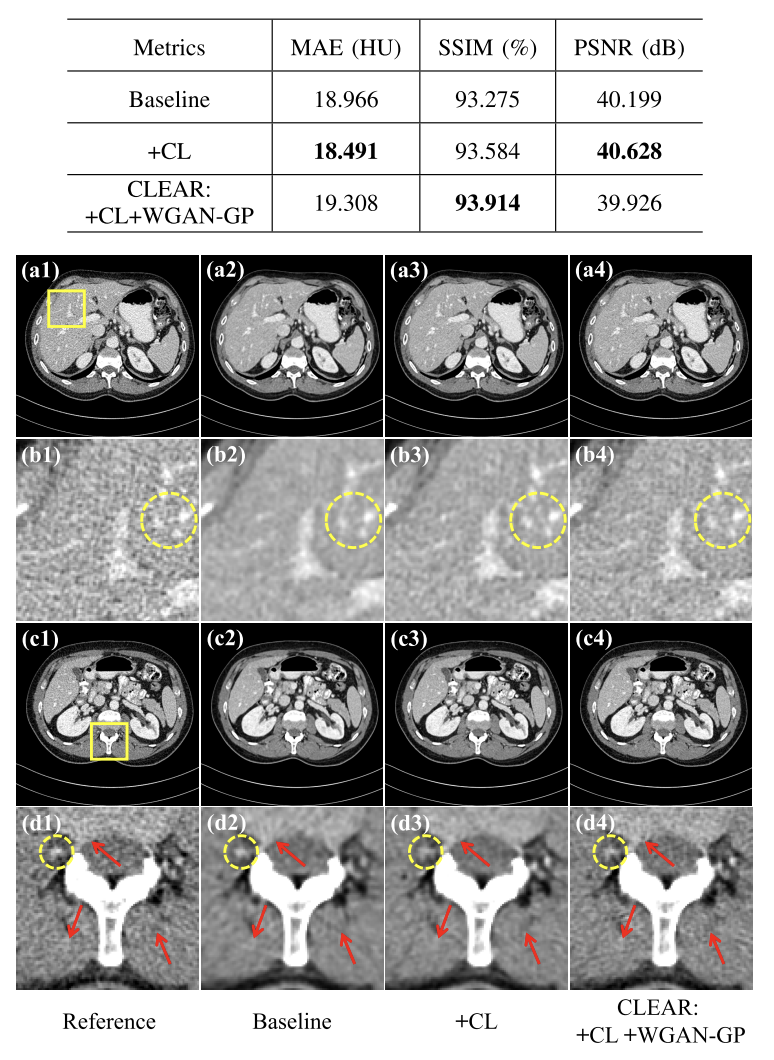

ablation study

- baseline : artifact (d2)

- CL 도입: artifact 억제, 과도한 부드러움 존재

- CLEAR:미세한 텍스처 보존, 시각적 인식 향상

정량적 평가

- 더 낮은 MAE와 PSNR

- 픽셀 단위의 손실을 최소화하도록 훈련-> MAE와 PSNR은 픽셀 단위 손실과 동일